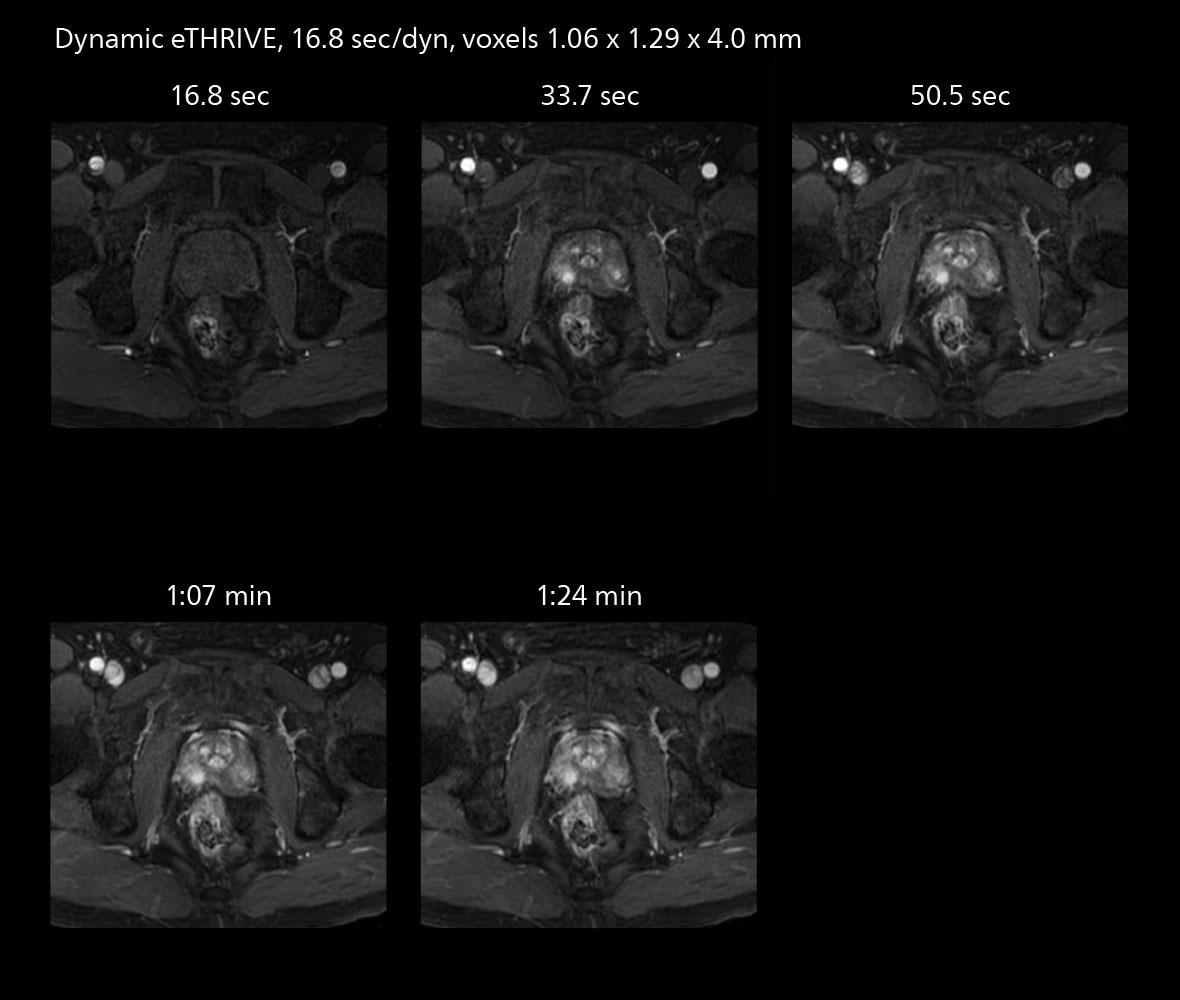

Examples of prostate imaging showing faster scan times and improved resolution illustrate the power of SmartPath to Elition X in this case of prostate cancer with PI-RADS score 4.